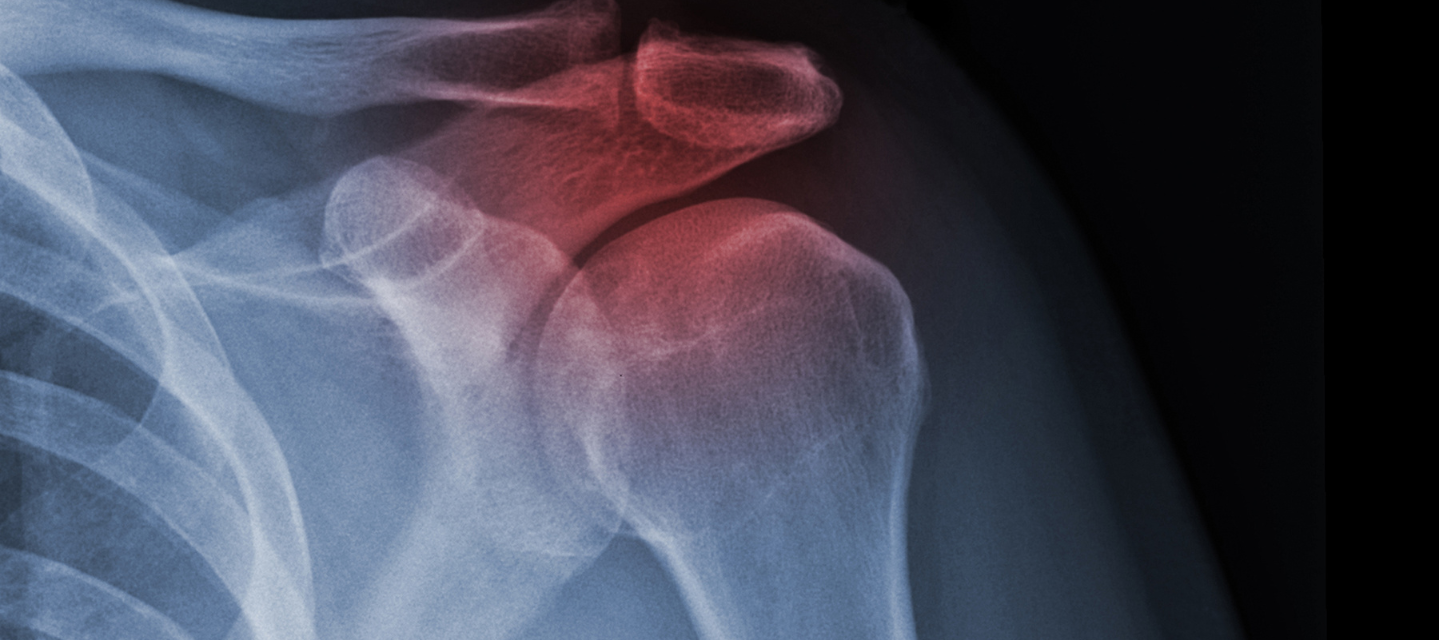

x-ray of human shoulder; radiation therapy program